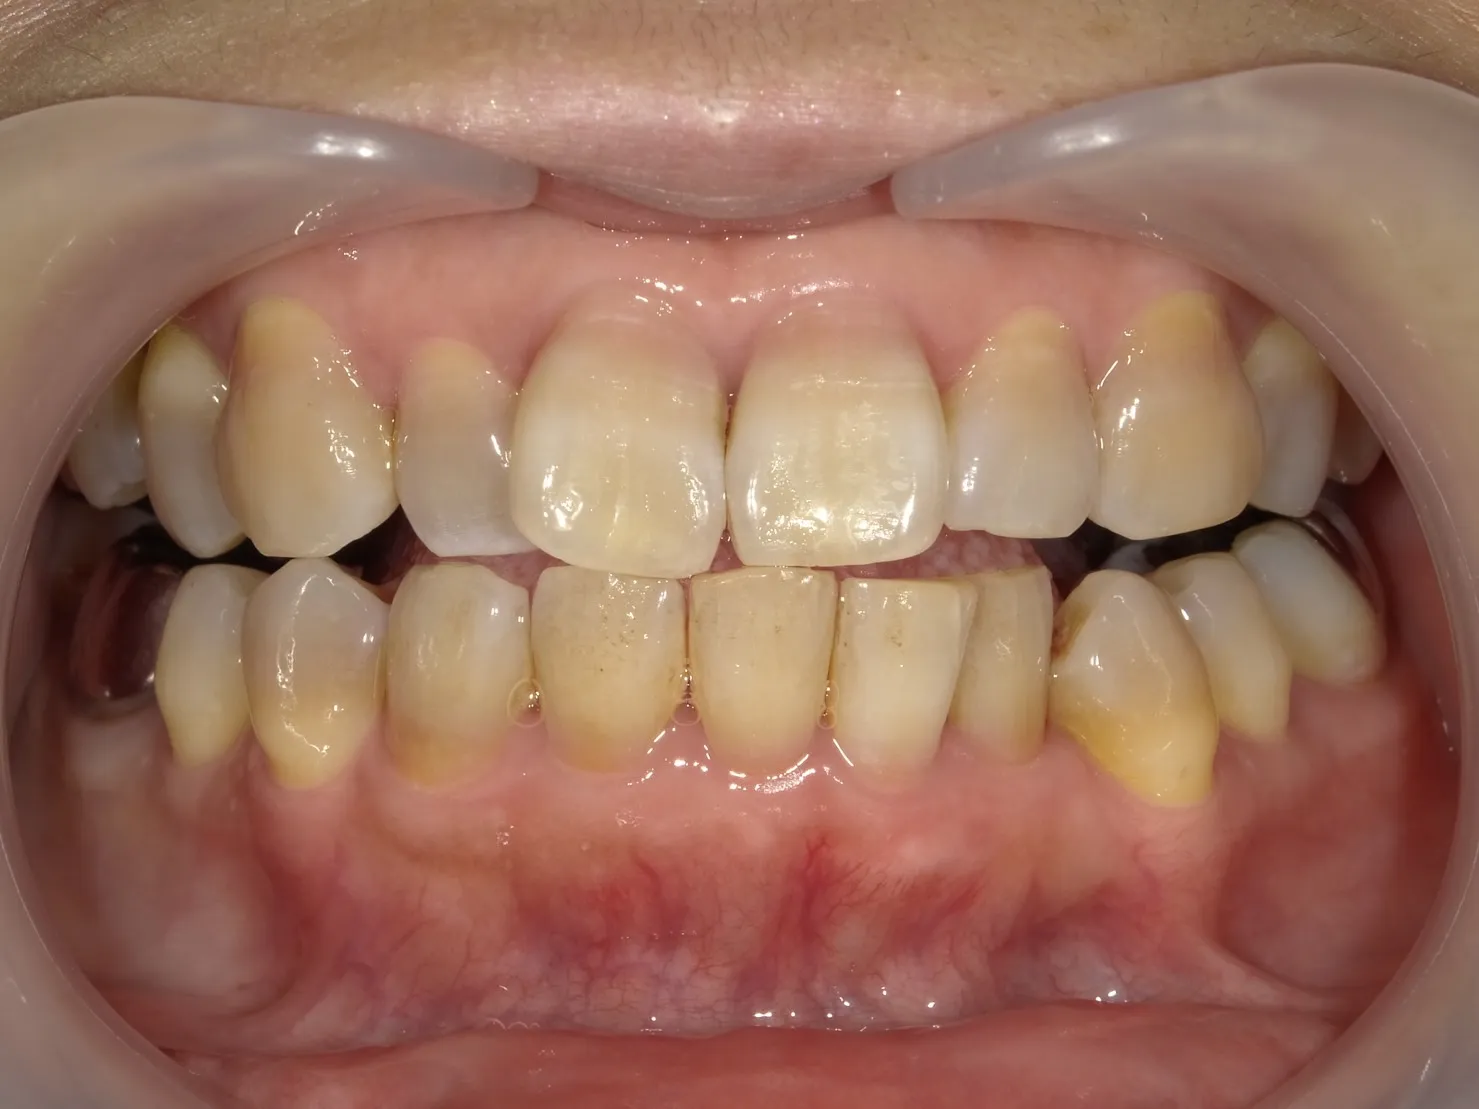

テトラサイクリン歯の特徴

深い着色

テトラサイクリン歯は、黄色から茶色、時には灰色の着色を示すことがあります。

この着色は歯の表面だけでなく、内部にまで及ぶことが特徴です。

不均一な着色パターン

テトラサイクリン歯の着色は歯全体に均等に現れるわけではありません。

歯によってはバンド状、斑点状、または不規則なパターンで現れることが特徴です。